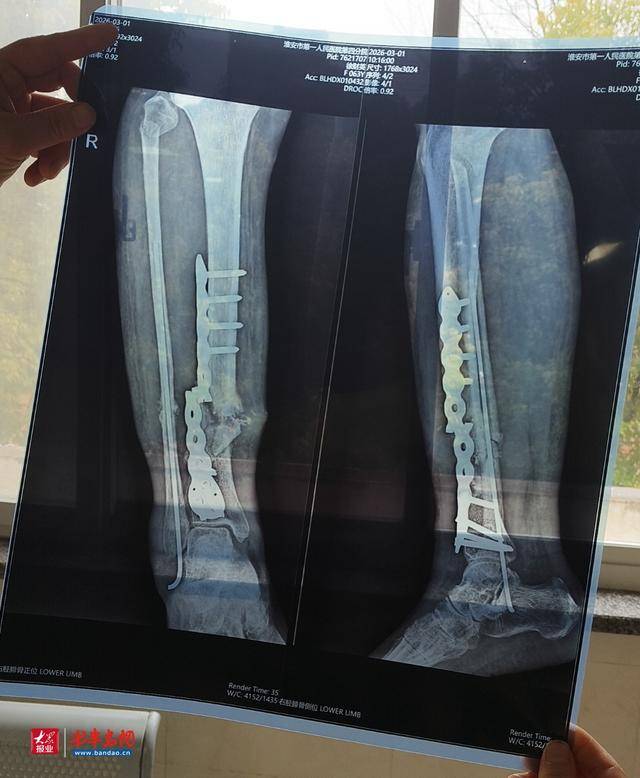

据尤先生介绍,2025年11月,其母亲因车祸导致腿部粉碎性骨折,在江苏沭阳铭和医院完成钢板内固定手术,住院两个月后出院回家静养。出院后老人一直严格遵照要求休养,可首次手术后,腿部持续肿胀数月始终没有缓解,给日常休养带来极大困扰。在首次手术后近四个月、出院即将满两个月时,老人仅在家中上厕所转身的瞬间,腿部突发剧痛,经检查确诊为体内钢板断裂,所幸骨折部位并未再次受损,骨头仍处于正常愈合状态。家属明确表示,事发前后老人从未从事重体力劳动,也没有摔倒、磕碰等任何外力情况,钢板无故断裂让他们难以接受。

事发后,家属与院方沟通二次手术事宜,院方要求必须先行缴费才能开展手术,无奈之下家属自筹费用,为老人完成了二次手术。更让家属质疑的是,第一次手术后持续数月的腿部肿胀,在第二次手术结束几天后便明显消退,这一情况让家属对首次手术的诊疗效果产生诸多疑问。

院方表示,患者出院时已明确告知,需从出院当天算起卧床休息3-4个月,相关告知均有书面记录可查,且患者本人也承认休养期间未遵医嘱、提前下床上厕所,这是导致钢板断裂的主要原因。院内专家分析认为,钢板在无不当外力作用下不会自行断裂,此次断裂系患者提前下床活动、遭受不当外力导致。

院方还称,已将专家讨论结果与患者沟通,虽患者不予认同,但已按规定封存相关病历及二次手术取下的断裂钢板,也告知患者可通过第三方鉴定确认钢板是否存在质量问题,如有质量问题将会进行补偿。同时,医院将积极向上申请,本着人道主义关怀原则,为患者酌情争取一定补助。